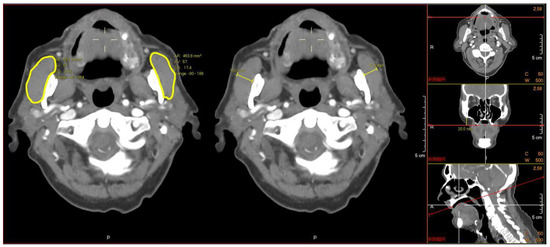

Measurements of the masseter muscle area and thickness were performed on preoperative CTs or CTAs of cervical and cerebral vasculature. All of the images were assessed through a picture archiving and communications system (PACS, AGFA Healthcare, Brentford, UK). All of the acquired scans had a slice thickness of 1–3 mm (mm), using a 512 × 512 matrix. Prior to conducting the measurements, adjustments in the tilt alignment of the CT scans were made according to a tangent along the lower borders of the arcus zygomaticus in the coronal plane and along the os palatum nasi in the saggital plane. Next, in the coronal view, the masseter muscle was identified 20 mm below the zygomatic arch. The outlines of the masseter muscle were manually traced bilaterally in the transversal images, and the maximum transversal diameter of the masseter muscles was measured at the same level (Figure 1). The imaging analysis program (PACS, AGFA Healthcare, Brentford, UK) calculated the area in square millimeters (mm2) and the masseter thickness in mm. The mean area and thickness, determined by measuring both of the masseter muscles, were used for analysis. In the analyses, low muscle mass, in this study referred to as low masseter muscle area (LMA) or low masseter muscle thickness (LMT), was defined as the mean masseter area or thickness of one standard deviation below the sex-based mean masseter area or the thickness of the study population [28]. Patients with a masseter muscle area or thickness above the cutoff-point of one SD below the sex-based mean were defined as adequate masseter muscle area (AMA) or adequate masseter muscle thickness (AMT).

Figure 1.

Example of performed measurements of bilateral masseter muscle area (left) and thickness (middle) after tilt adjustments were performed (right).